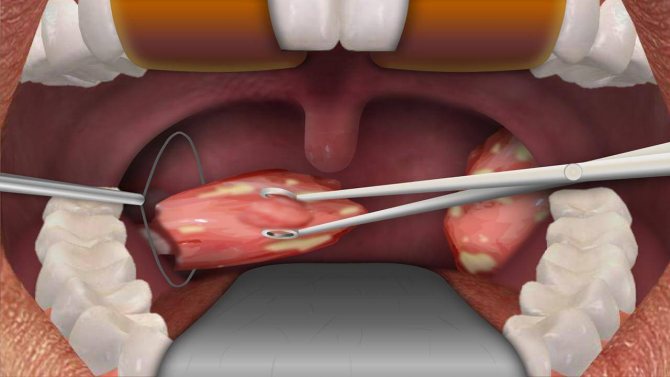

Хирургическое лечение

Если фолликулярная ангина повторяется с неприятной регулярностью, с каждым разом протекает все интенсивнее и болезненнее, приносит много страданий больному и оставляет после себя осложнения, единственным остающимся выходом становится оперативное вмешательство.

Врачи считают миндалины своеобразным естественным фильтром, которые не пропускают разнообразные болезнетворные микроорганизмы дальше горла. Именно поэтому в наши дни миндалины удаляют только в крайних случаях, когда польза от их отсутствия будет намного больше, чем при их наличии. Раньше же считалось, что единственным вариантом лечения ангины с серьезными проявлениями является операция.

Хирургическое удаление миндалин практикуется в крайних случаях. Обычно назначаются процедуры оперативного свойства только при неэффективности консервативных методов. Важно не упустить момент.